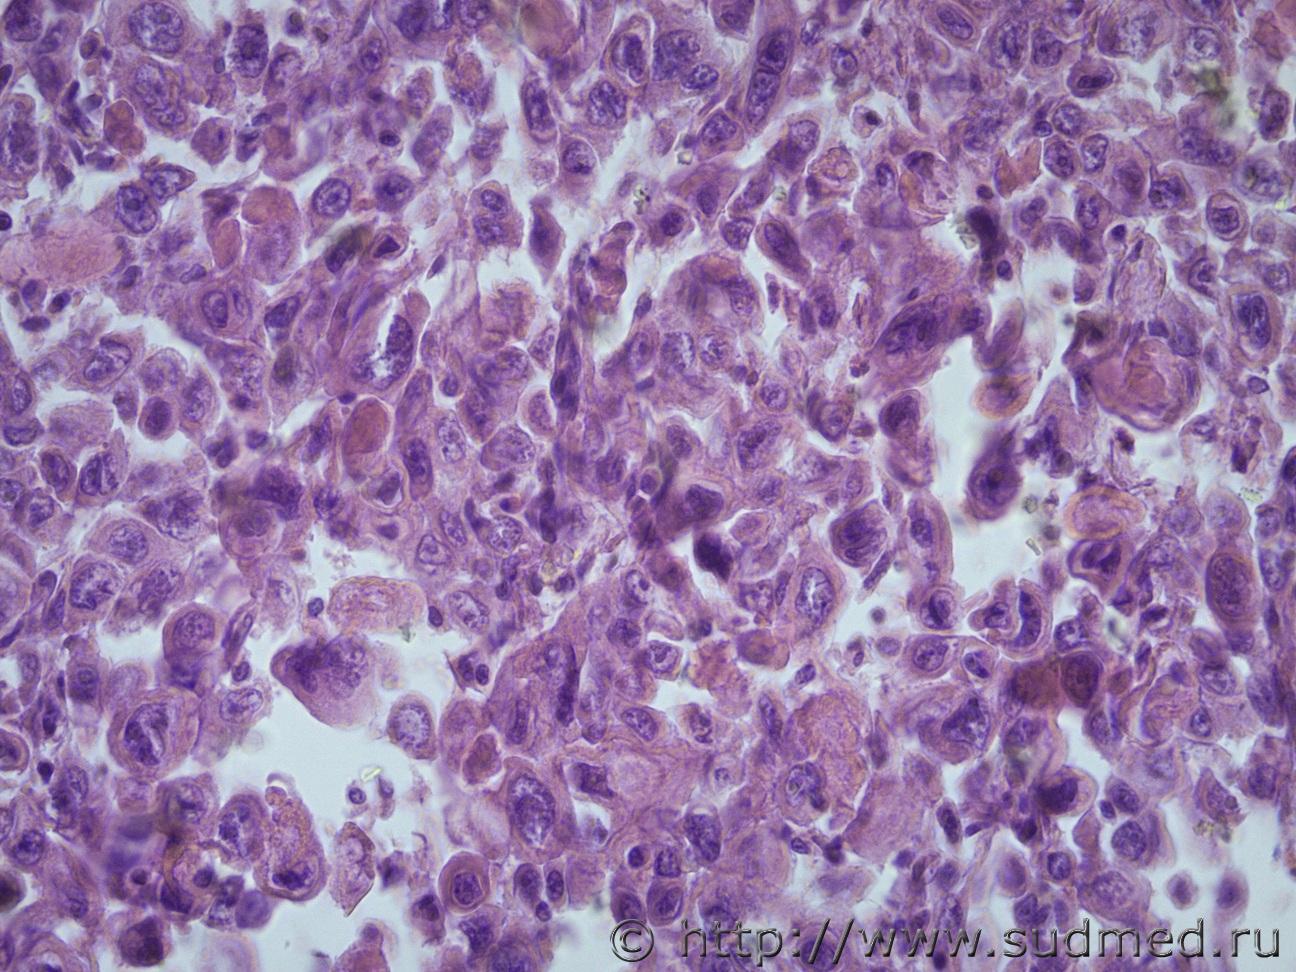

Ув. коллеги помогите пожалуйста определиться с опухолью примой кишки Судебная медицина - Прикрепленное изображение Судебная медицина - Прикрепленное изображениеСудебная медицина - Прикрепленное изображениеСудебная медицина - Прикрепленное изображениеСудебная медицина - Прикрепленное изображение

Что-то недифференцированное.

Я вижу амебу только!

Жен 80 лет. Эксперт видит только это образование, без метастазов. Описывает как опухоль прямой кишки с прорастанием в стенку мочевого пузыря. На гистологию прислал узел 5х5 см, плотно эластический, белого цвета.

Недифференцированная карцинома.

По 1 фото подумал про криптококков. Но ядра... И впрямь амебный абсцесс?

Браво !

Подскажите пожалуйста хорошую литература с патоморфологией по амебиазу. Нашла пока только патологическая анатомия амебиаза С.М Полякова, М.К. Недзьведь. Может есть еще что-то лучше. Амеб тоже вижу, но мне кажется, что много патологических клеток с патологическими метозами, есть капсула; может ли такое быть при амебиазе, амебоме?

Коллега! Режим диафрагму наоборот передвинуть нужно. В последнем снимке все таки наблюдается лимфопролиферативный процесс.....